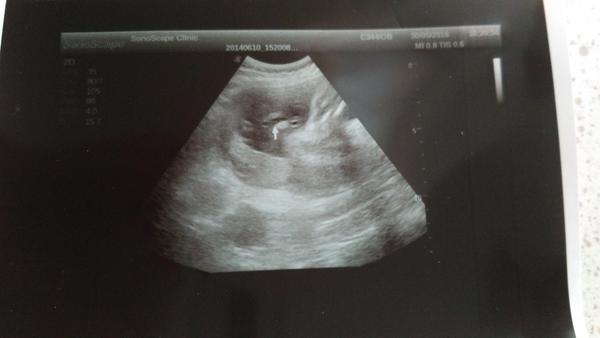

Je to holčička nebo chlapeček? Foto ultrazvuku

Pro neho neni dulezity co to bude ale jestli to bude zdrave ale to uz vime proteze mame genetiku za sebou . 😉 .okolo patere dole tak mi tam vidime devcatko ale vhtela sem vedet jeste nejaky nazor . tak dekuji . moc

Doktor jen řekl, že tam pindíka nevidí. Ale jestli je to kluk nebo holka vyloženě neřekl. Nemůžu si pomoct, ale cítím se na kluka. Je to úplně jiné těhotenství, než s první dcerou. Prostě pravý opak všeho. Tady mi jde o to, že jsem viděla dva skoro totožné ultrazvuky, tvrdily také, že je tam jasné kávové zrno a oni se z toho vyklubali kluci jako buci ☺

@ellilenka já si myslím, že kdyby to byl kluk, tak už by tam pindíka viděli a pokud neviděli, tak je to jasná holčička 🙂 a nebo ještě počkat na další velký utz ve 30.tt a tam si říct ať se zaměří i na pohlaví 🙂 mě to na 100% potvrdili na 4D utz